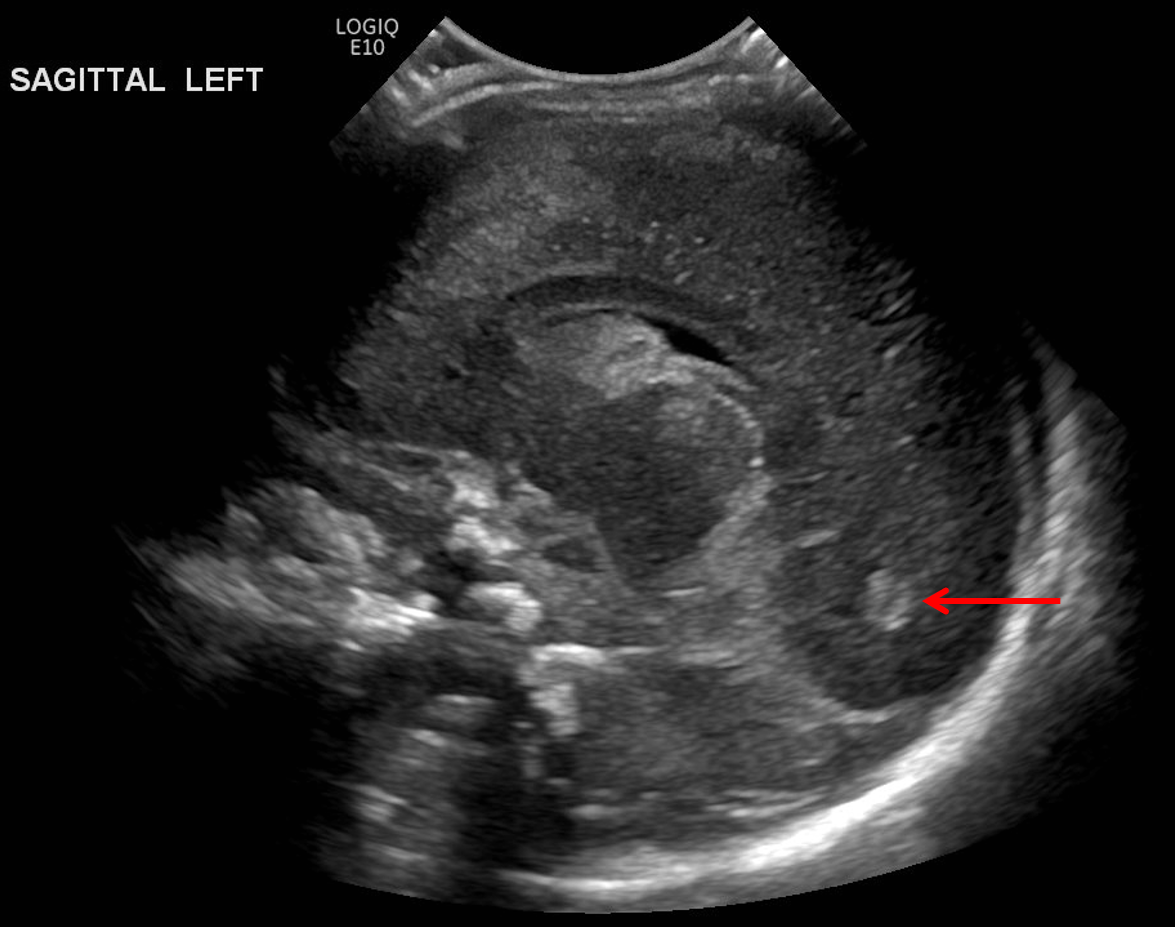

Age: 4 days (born at 24 weeks)

Sex: Male

Indication: Evaluate for germinal matrix hemorrhage

Grade 2 germinal matrix hemorrhage

Sample ReportLeft germinal matrix hemorrhage involving the caudothalamic groove and layering in the occipital horn of the left lateral ventricle without hydrocephalus (grade 2).

No abnormal brain parenchymal echogenicity or extra-axial collections.

Premature sulcation pattern.